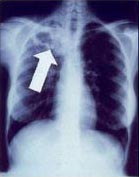

Tuberculosis creates cavities visible in x-rays like this one in the patient's right upper lobe.

In active pulmonary TB, infiltrates or consolidations and/or cavities are often seen in the upper lungs with or without mediastinal or hilar lymphadenopathy.[1] However, lesions may appear anywhere in the lungs. In HIV and other immunosuppressed persons, any abnormality may indicate TB or the chest X-ray may even appear entirely normal.[1]

5. Hilar or mediastinal lymphadenopathy (bihilar lymphadenopathy) - Enlargement of lymph nodes in one or both hila or within the mediastinum, with or without associated atelectasis or consolidation.